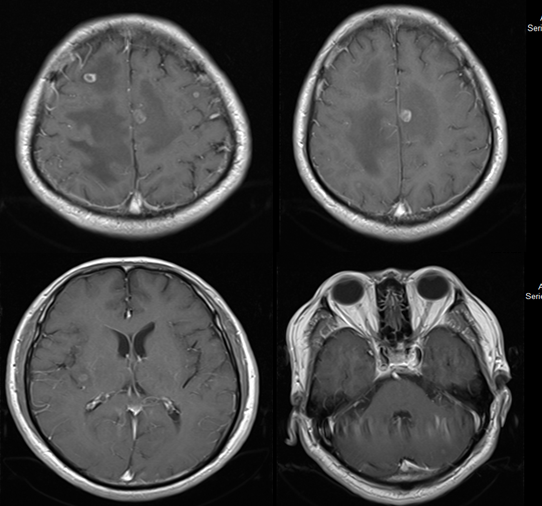

2019年4月16日开始给予信迪利单抗(200mg,q3w)+阿帕替尼(250mg,qd)治疗,治疗1周期后,患者症状明显改善,2周期后复查CT,疗效评价为部分缓解(PR;图3-4)。治疗期间患者出现1-2级皮疹,未观察到其他副作用。

image004.png

图3.患者2019年5月18日头部CT影像资料